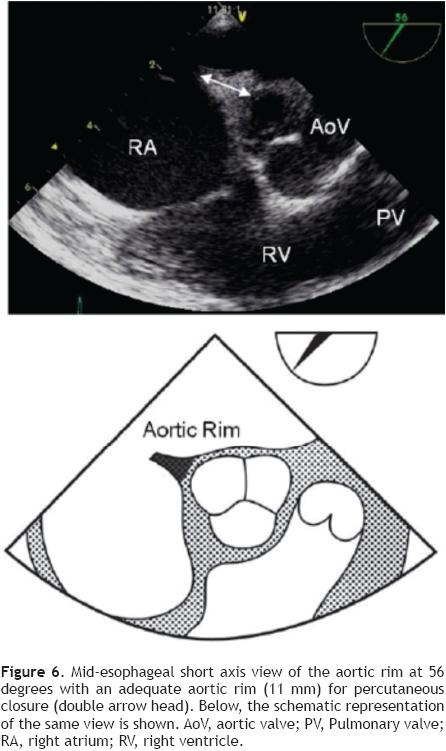

To achieve proper visualization of the Ao (Figure 6), the probe must be at a mid-esophageal level, at 45° with a leftward (counter-clockwise) rotation of the probe to allow simultaneous visualization of the aorta (AA) and the ASD. Sometimes the Ao is very small, or even absent (Figure 7), this finding makes the procedure more challenging but does not, preclude PTC of the defect.